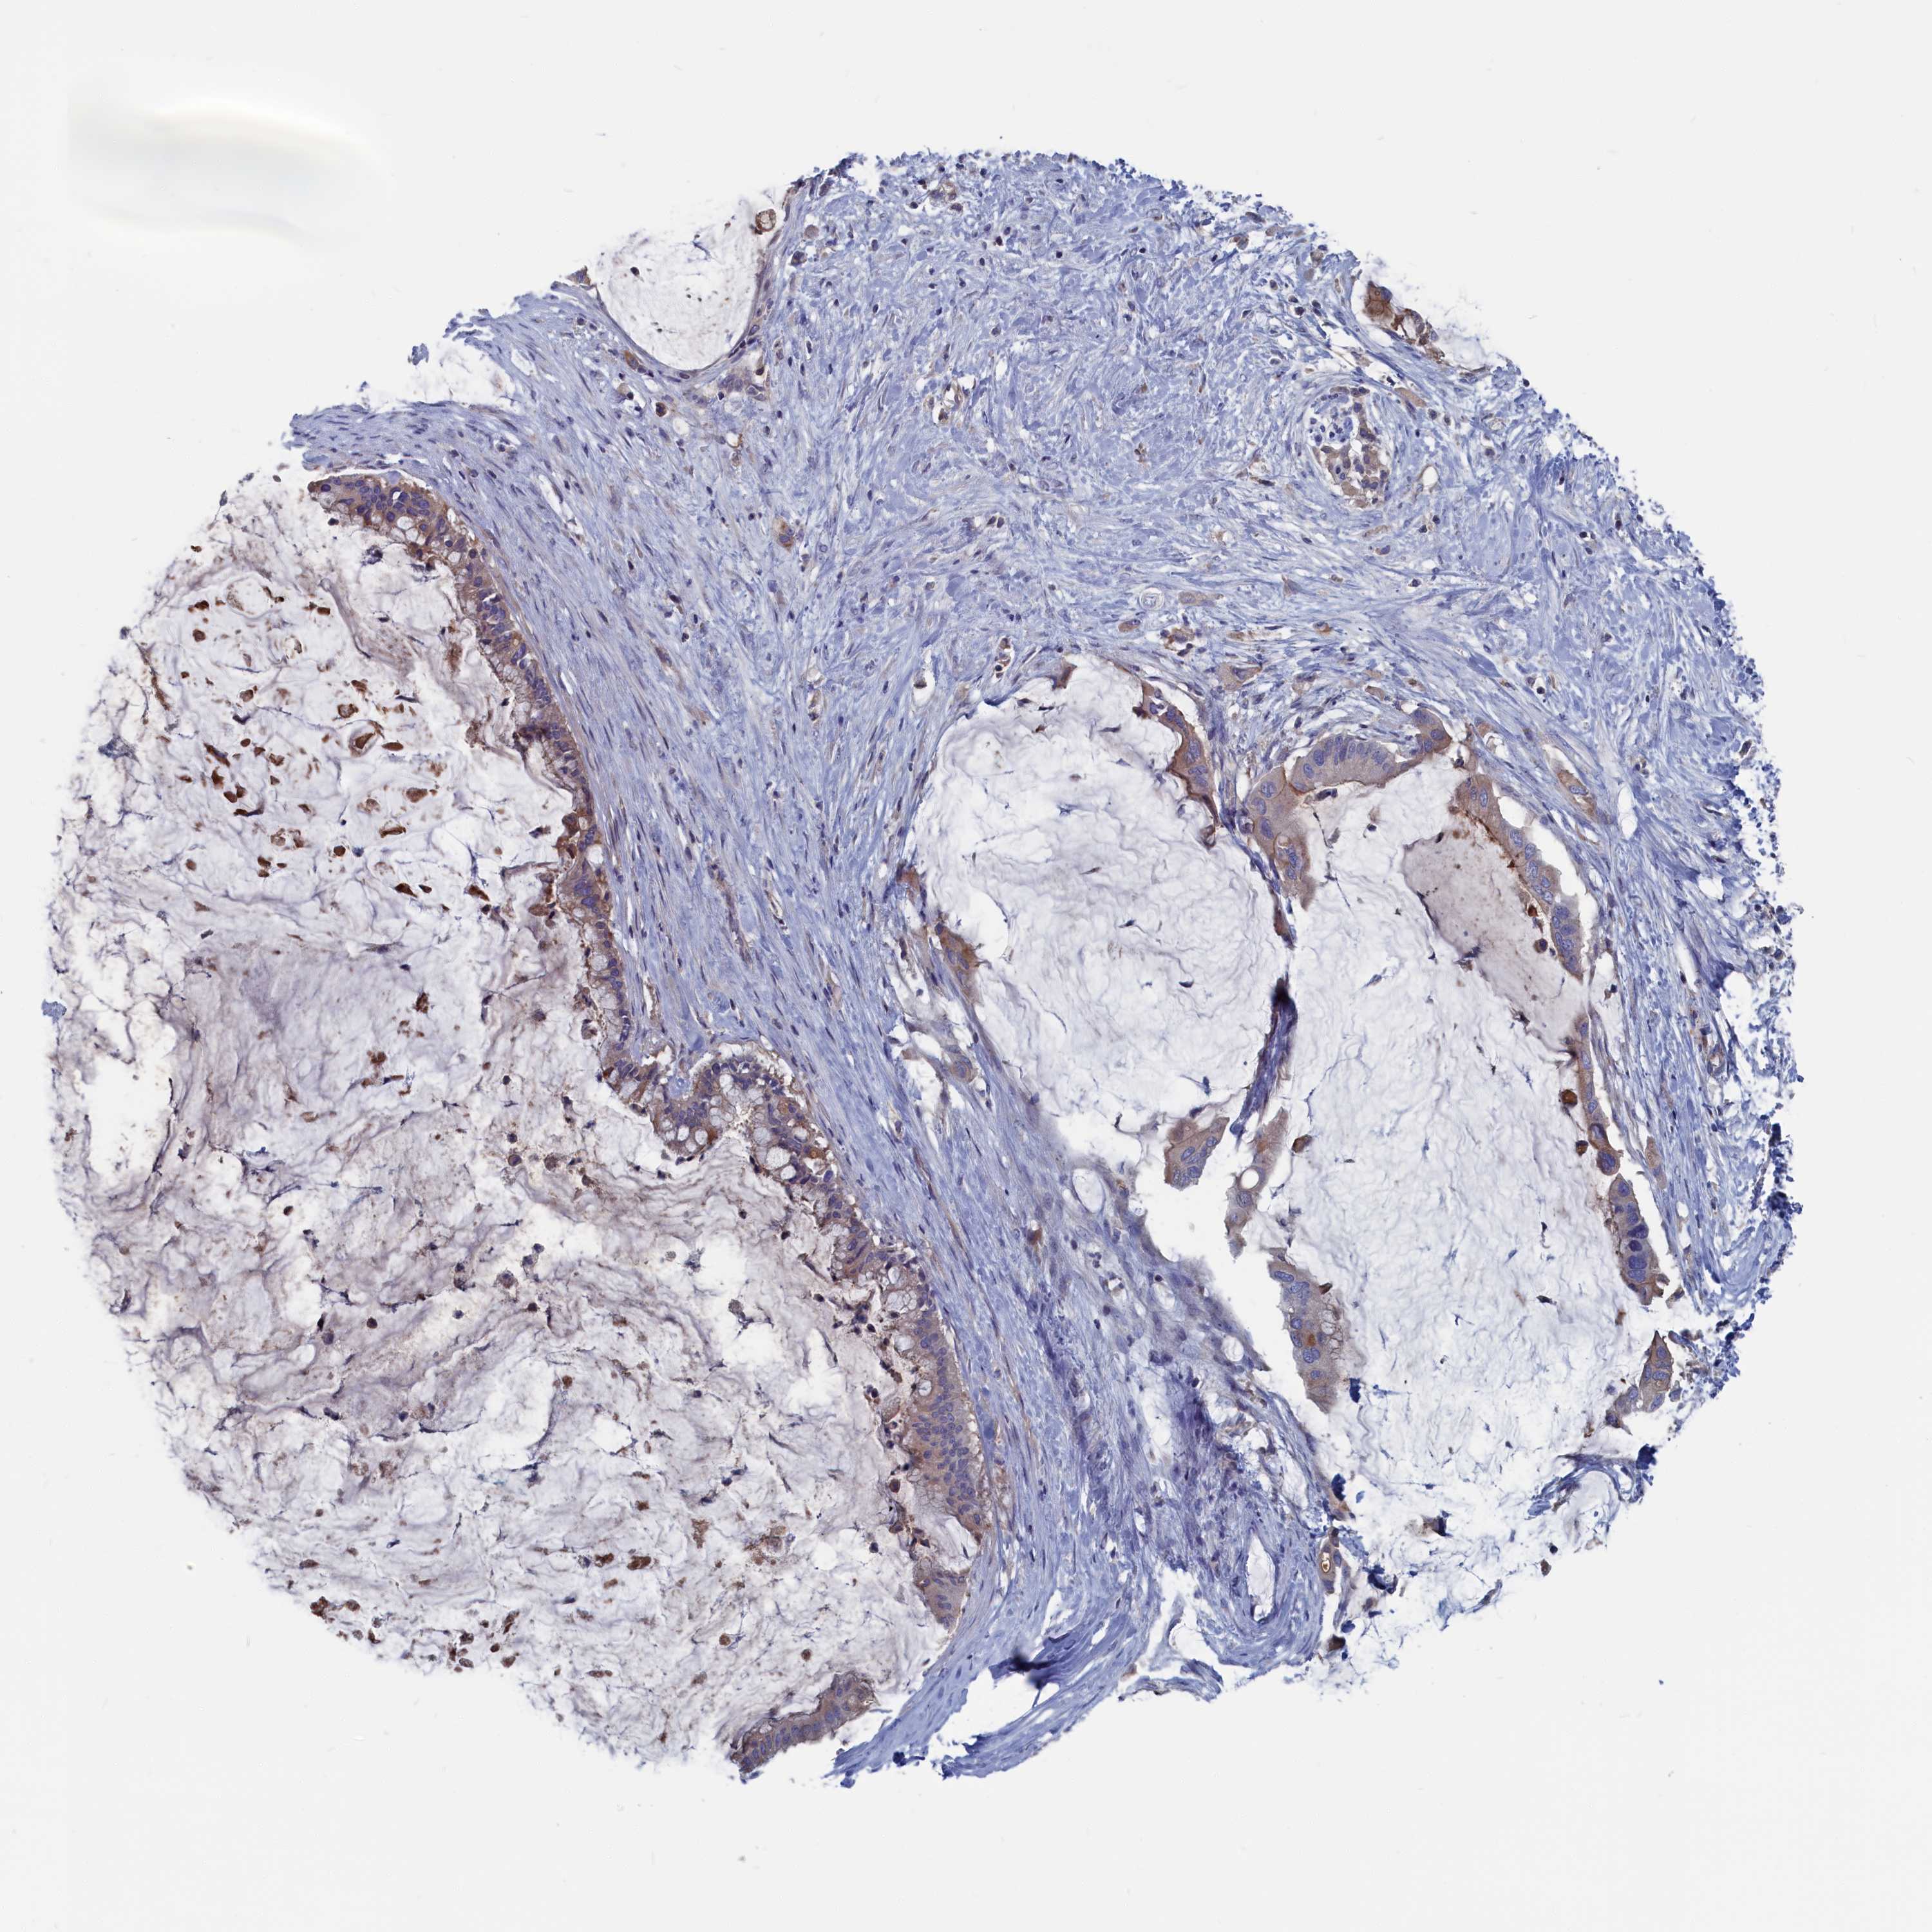

PANCREATIC CANCER - Protein expressioni

A mouse-over function shows sample information and annotation data. Click on an image to view it in a full screen mode. Samples can be filtered based on level of antibody staining by selecting one or several of the following categories: high, medium, low and not detected. The assay and annotation is described here.

Note that samples used for immunohistochemistry by the Human Protein Atlas do not correspond to samples in the TCGA dataset.

Antibody stainingi

Antibody staining in the annotated cell types in the current human tissue is reported as not detected, low, medium, or high, based on conventional immunohistochemistry profiling in selected tissues. This score is based on the combination of the staining intensity and fraction of stained cells.

Each image is clickable and will lead to virtual microscopy that enables deeper exploration of all samples and also displays staining intensity scores, fraction scores and subcellular localization as well as patient and tissue information for each sample.

Antibody HPA042527

Staining

High

Medium

Low

Not detected

Intensity

Strong

Moderate

Weak

Negative

Quantity

>75%

75%-25%

<25%

None

Location

Nuclear

Cytoplasmic/membranous

Cytoplasmic/membranous,nuclear

Adenocarcinoma, NOS